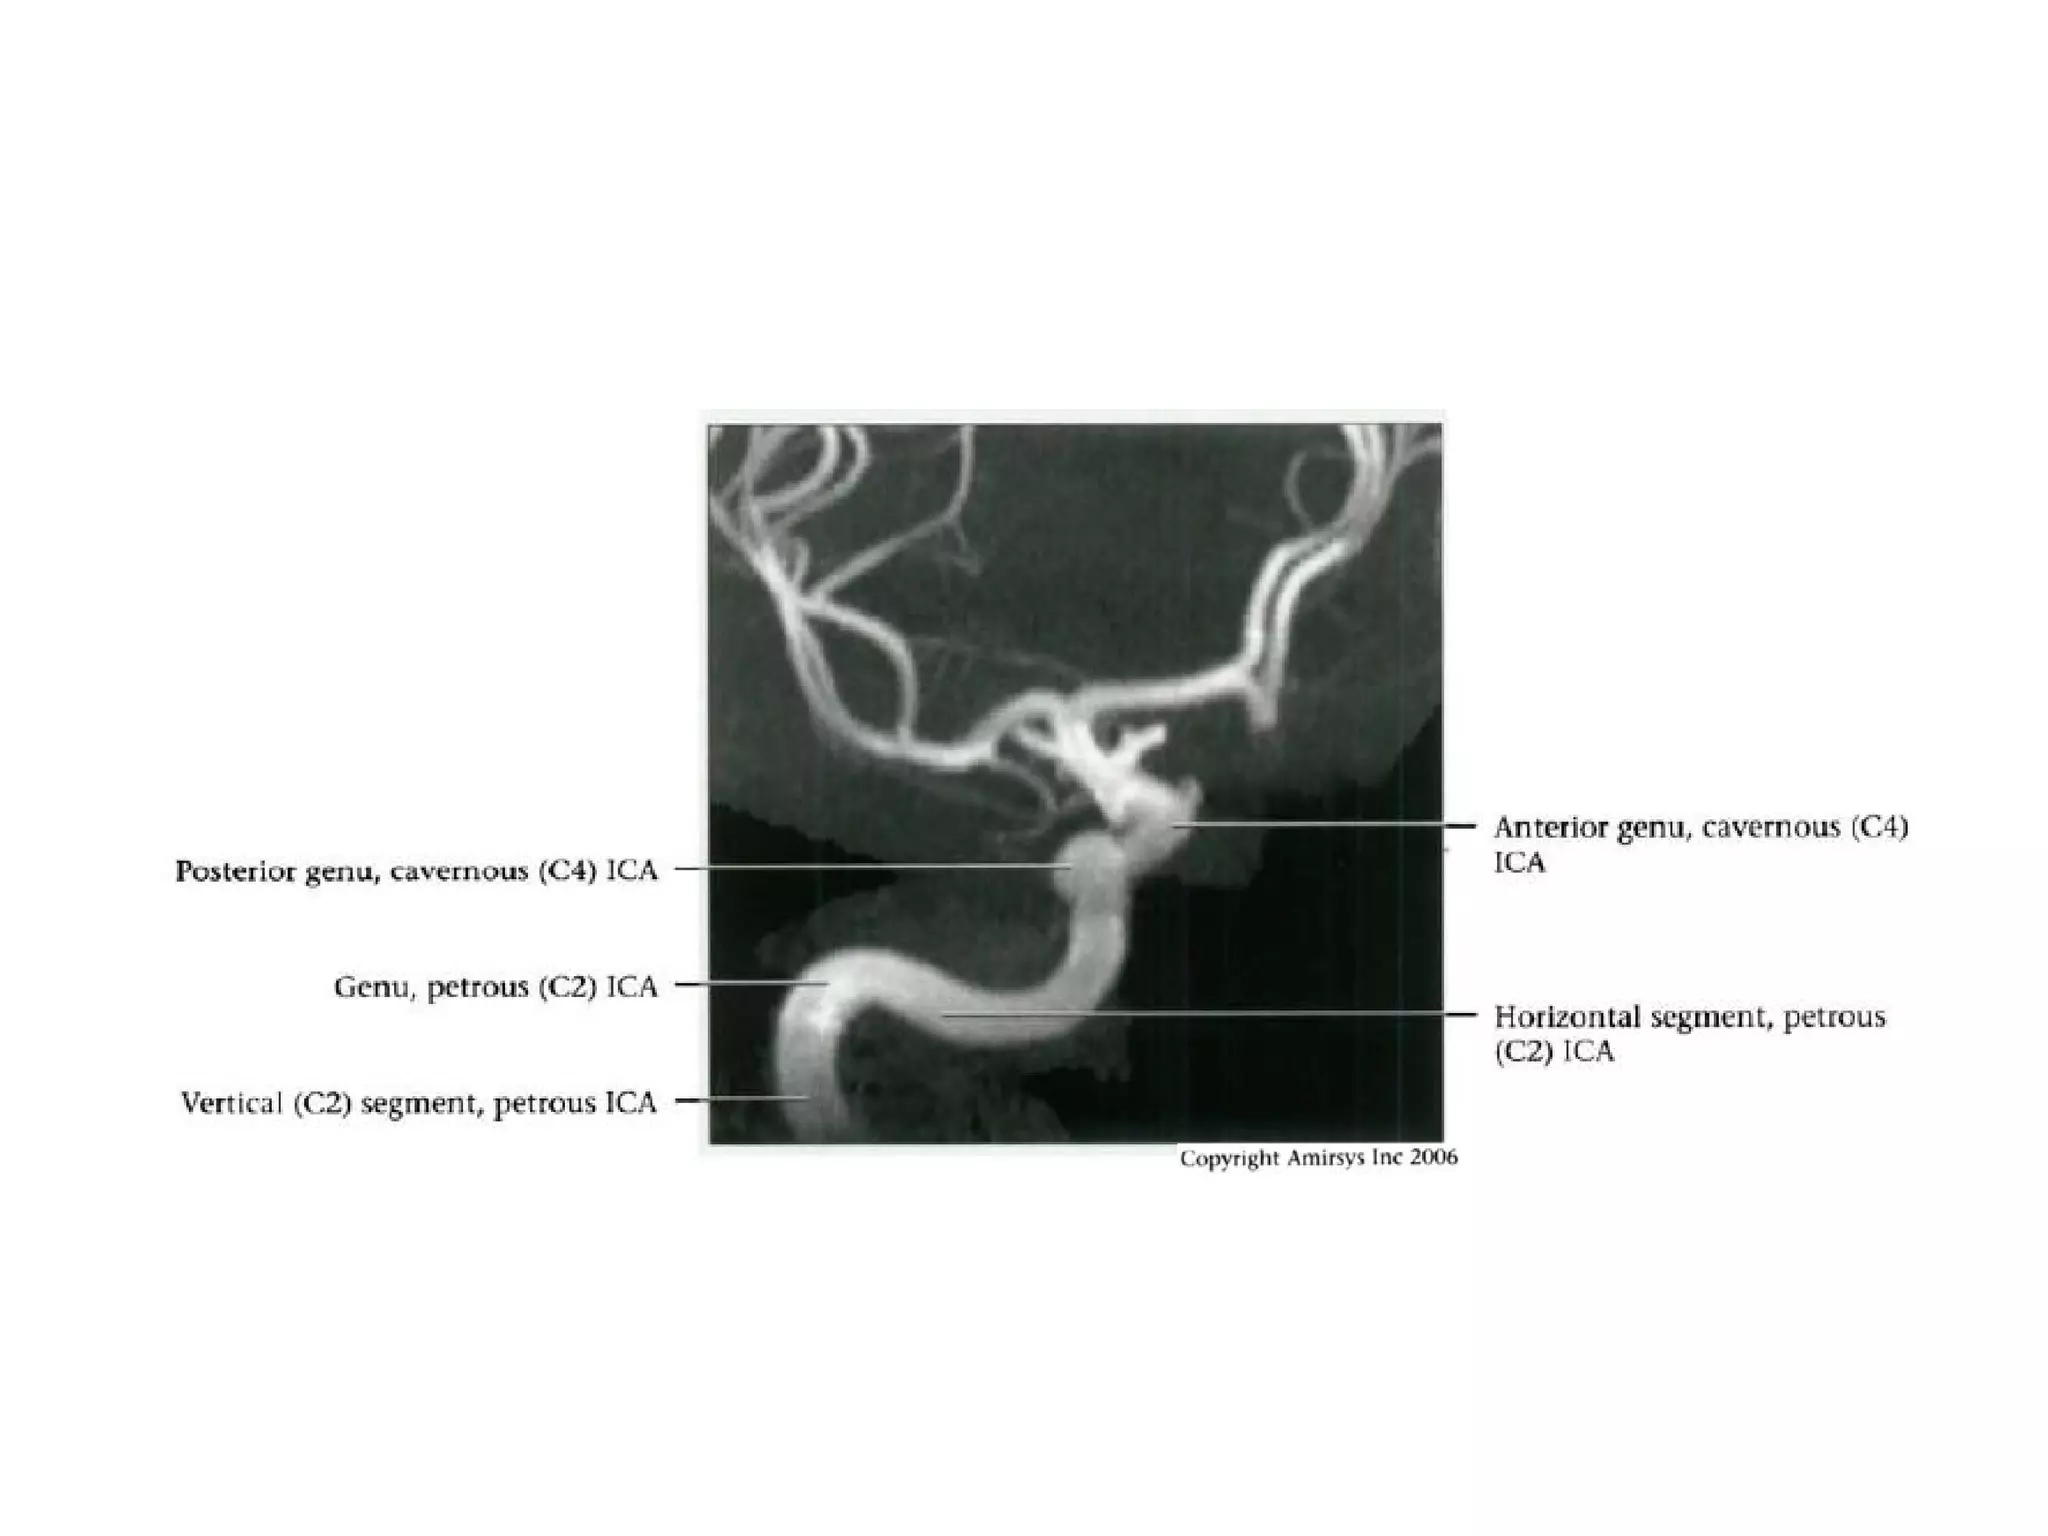

INTRACRANIAL INTERNAL

CAROTID ARTERY

Overview

• Complex course with several vertical /

horizontal segments, 3 genus (one

petrous, two cavernous)

• Six intracranial segments (Cervical lCA =

C1):

- Petrous (C2), Lacerum (C3),

Cavernous (C4), Clinoid (C5),

Ophthalmic (C6), Communicating (C7)

Petrous (C2) segment

• Contained within carotid canal of temporal bone

- Surrounded by extensive sympathetic plexus

- Two C2 subsegments joined at genu

• Short vertical segment - anterior to internal jugular vein

(lJV)

• "Genu" (where petrous ICA turns anteromedially in front

of cochlea)

• Longer horizontal segment

- Exits carotid canal at petrous apex